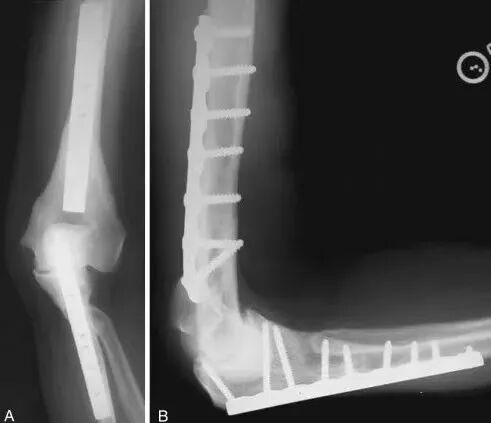

早期的AO技术

AO最早是90-90度钢板的派系,与平型钢板打的火热,后来没打过

1.钢板的形态没有特殊特定的,需要塑性预弯尤其在控制远端的骨折块的时候,钢板和螺钉的角度都必须十分讲究2. 对于滑车的固定只能应用最远端的拉力螺钉,与钢板不能连接3.这种固定在肱骨髁之间无法完成较好的骨折块之前的加压固定

所以对于这样固定的患者就面临一个问题,如果敢早期锻炼,就可能愈合不良,如果石膏固定时间长的话,肘关节就会僵硬

基于应用AO技术的话,固定要点1.一定要将钢板尽量往远端放,把远端骨块固定好2.髁间的固定一定要坚强,加压!3.尽量的坚强固定4.固定基础下早期功能锻炼

AO固定技术流程1.复位时,先把滑车固定好,可应用空心螺钉.

2.然后用克氏针将骨折块经过钢板来进行固定,注意钢板一定要把远端包裹一点。

3.先用普通螺钉固定肱骨近端的孔,完成临时固定,不用拧太紧。

4.然后进行远端的单侧加压固定

5.应用大巾钳和加压螺钉完成髁间的加压固定

具体办法:用大巾钳完成两侧柱的加压后应用螺钉完成固定

同样的完成对侧的固定

7.最后完成其他的螺钉锁定,形成一个完成的肱骨远端力学结构

远端螺钉尽量打满,完成髁间的链接,近端3个以上螺钉。

髁间一定要有链接的长螺钉(对角线螺钉)

以上就是AO技术的基本流程,髁间加压技术对骨折的愈合十分重要!